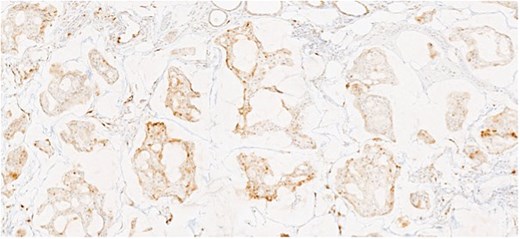

Herein, we present a 75-year-old man who, having been referred to our service with an inguinal hernia, raised concern about a palpable mass present in his right axilla. The main differential on initial examination was that of a simple epidermoid cyst, and consent was obtained for its removal during his elective hernia repair. Subsequent histology however, revealed a well differentiated MAC. There was extensive involvement of the deep and superficial reticular dermis (Figs 1and 2). Lymphovascular invasion was present. Sweat glands were focally involved by the carcinoma. The differential diagnosis included PCMC and metastasis from other primary sites of MAC such as breast, lung and gastrointestinal. Immunohistochemical profiling was performed on the specimen. CK 7, HER2 (4B5, 3+), GATA3 (strong, diffuse), and P16 (focal, weak) were positive (Figs 3–6). SOX10, CK 20, CDX2, TTF-1, p40, ER, and PR were negative which supported the diagnosis of MAC with either breast or PCMC origin based particularly on GATA3 expression.